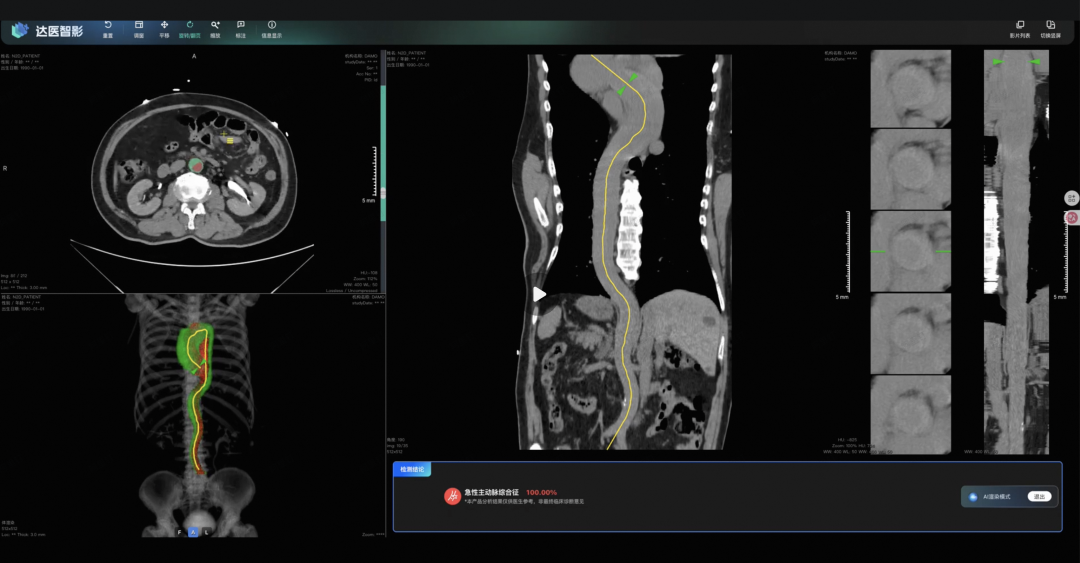

浙大一院与达摩院组建联合研究团队开发的这个识别主动脉综合征的大模型iAorta,来了。

他们的AI模型iAorta真正做到了不可能完成的任务,利用普通平扫CT,精准识别主动脉综合征。

他们把模型部署到了上海一个大三甲医院,在一个为期两个月的临床试验里,AI从一万五千多名胸痛患者中,精准地揪出了21个主动脉综合征患者,敏感性达到95.5%,特异性达到99.4%。

敏感性95.5%,意味着100个真病人,它能找出将近96个,几乎不会漏诊。特异性99.4%,意味着它极少冤枉一个好人,不会给医生添乱。

这21名患者,从入院到最终确诊,平均只花了1.7个小时。而国际上的平均确诊时间是多少?4.3个小时。

这里面有个案例特别典型。一个43岁的病人因为上腹部钝痛入院,医生初步怀疑是胆囊结石,就开了个上腹部的平扫CT。结果片子刚拍完,大概3分钟,iAorta就报警了,说主动脉有夹层的迹象。

医生马上跟进做了增强CT,确诊!整个过程只用了94分钟。